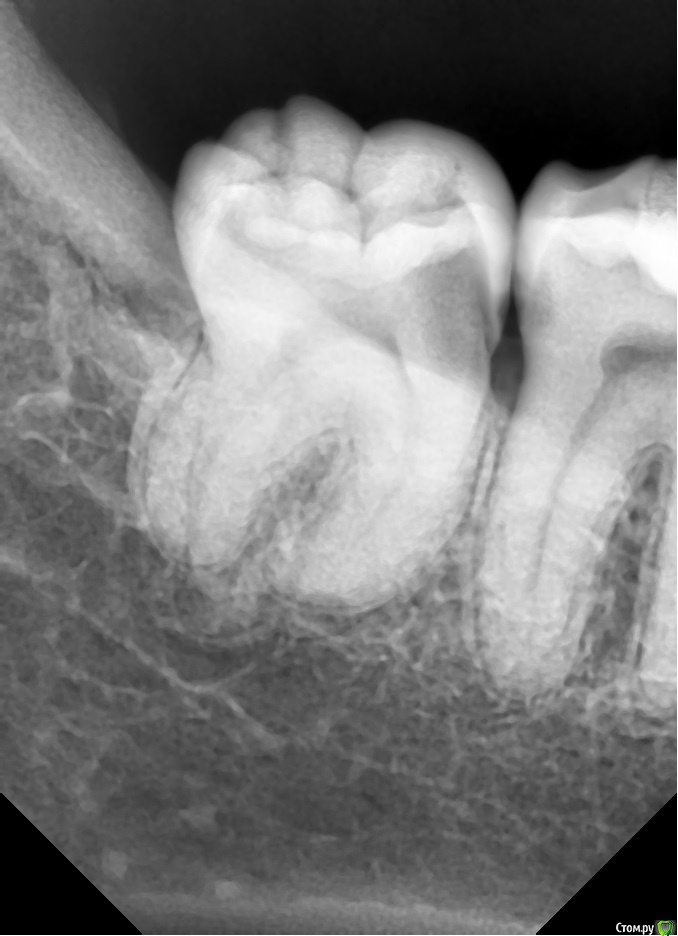

St. Опубликовано 3 февраля, 2016 Поделиться Опубликовано 3 февраля, 2016 Коронки на живые зубы в прогнозе действительно лучше, но по Вашему снимку кариес достаточно глубокий и есть довольно высокая вероятности хронического пульпита в 6 зубе. Я бы первоначально убрала весь кариес и заменила пломбы или восстановила и временные коронки. И понаблюдать пару недель. Если в процессе вскроется "нерв" или разболится - тогда конечно депульпировать.Р.С. Меня как-то очень смущает методика Обтачивать собирается за несколько раз понемногу, чтобы "не перегревать нерв" за 4-6 раз. . 3 Ссылка на комментарий

horoshie.veshi Опубликовано 4 февраля, 2016 Автор Поделиться Опубликовано 4 февраля, 2016 (изменено) Вам уже предложили вариант, начинайте с лечения. Так этим и занимаюсь. Сегодня вычистили полностью 8 (абсолютно спокоен) и 7 со стороны их контакта. Попросила еще снимки переделать до начала лечения, чтобы не было половины "отрезанных" зубов... http://s015.radikal.ru/i332/1602/7e/ff3dd3436447.jpg http://s019.radikal.ru/i640/1602/e1/69b726316ccd.jpg 7 с его небольшой полостью со стороны контакта в принципе, до пульпы-то далеко, но в процессе к концу третьего часа начал ощутимо колоть на бормашину и воздух + десна раскровилась, и вот сейчас поднывает, но терпимо... Даже, если допустить, что эти ощущения от "растревоженности" через несколько дней уйдут, не уверена я что-то в своем желании проходить его обточку живым, чтобы не то, что 6 раз, а даже пару-тройку это терпеть... С другой стороны депульпирование и чистку каналов я тоже переношу очень болезненно, никогда еще не было так, чтобы не подпрыгивала в кресле от боли, "уколы" сильные и глубокие, их не снимает даже двойная доза Ультракаина... Трудный выбор. Депульпировать можно в субботу, когда будем делать 6 и 7 со стороны контакта... Изменено 4 февраля, 2016 пользователем horoshie.veshi Ссылка на комментарий